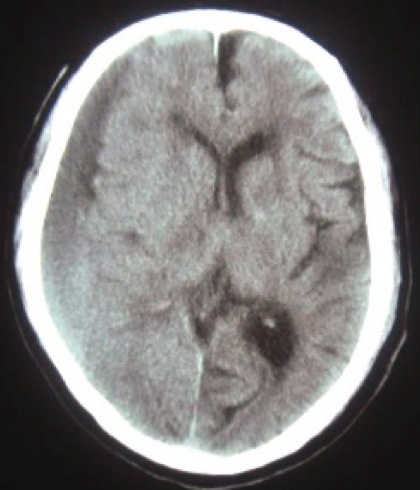

軽い頭部打撲や転倒をきっかけに脳内に出血がおこり、血種となることにより脳機能に障害を及ぼす病気です。急速な症状の悪化がみられる場合があります。